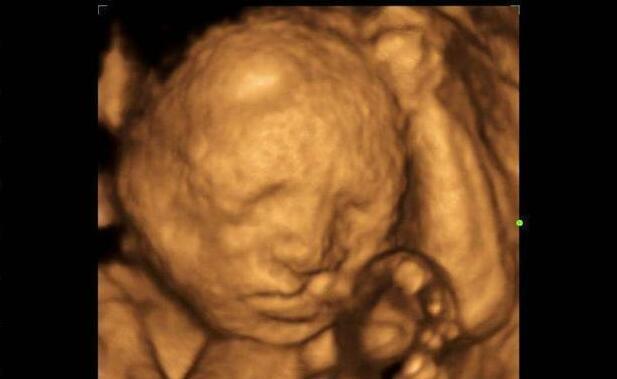

很多朋友在孕中期的时候,会选择四维彩超来进行大排畸检查,除了检查清晰度高之外,最大的目的就是能够保存胎儿的照片留作纪念,但是四维照片实在是太丑了,经常把孕妈们吓得怀疑人生,这么丑的胎儿真的是我的宝宝吗?

这不刚刚有位准爸爸私信说:老婆怀孕24周,大排畸检查的时候提前预约的四维彩超,都说四维彩超可以留照,但是拿到照片以后,却发现照片里的胎儿鼻子嘴巴特别大,看起来丑的不得了,孩子生出来以后真的这么丑吗?

四维彩超的检查时间是孕22-28周,此时的胎儿还没有足月,小小的一只,浑身皱巴巴的,还没有发育完全;同时胎儿的身上还有一层厚厚的胎脂,这些胎脂让胎儿的皮肤看起来凹凸不平,拍摄的时候,自然会影响到照片,让胎儿的鼻子嘴巴看起来特别大。